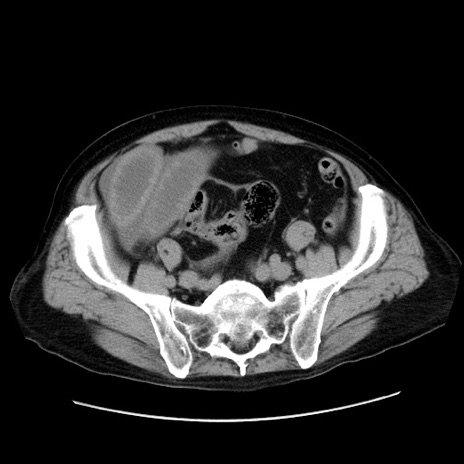

症例30(横断像)

【症例】80歳代男性

【主訴】臍周囲痛

【現病歴】約6時間前から臍下部痛が出現。次第に腹部膨隆・背部痛も生じてきたため来院。背部痛の場所は変化しない。

【身体所見】意識清明、BT 36.3℃、BP  131/87mmHg、P 87bpm、SpO2 100%(RA)、臍周囲自発痛・圧痛あり、反跳痛なし、自発痛部位に一致して板状硬あり、腹部膨隆、腸雑音減弱、CVA tenderness両側陰性。

【データ】WBC 19600、CRP 0.33